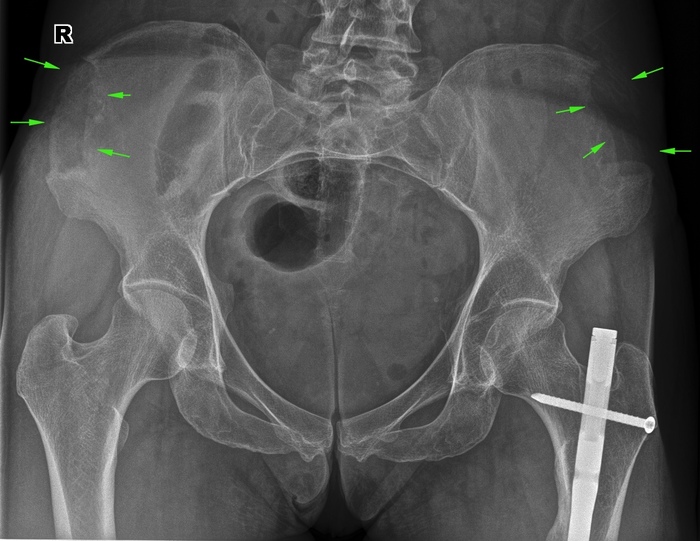

Еще один снимок таза, в котором можем наблюдать сразу три выраженных патологии (артроз тазобедренных суставов тут тоже есть, но про артрозы будет отдельный пост):

- множественные камни в мочевом пузыре

- культи обеих бедренных костей после ампутации в следствии обморожения

- выраженное обызвествление бедренных артерий